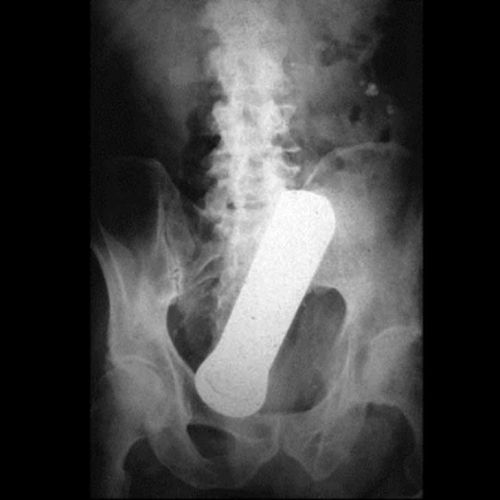

Os objetos mais BIZARROS encontrados no ânus pelos médicos

Lanterna